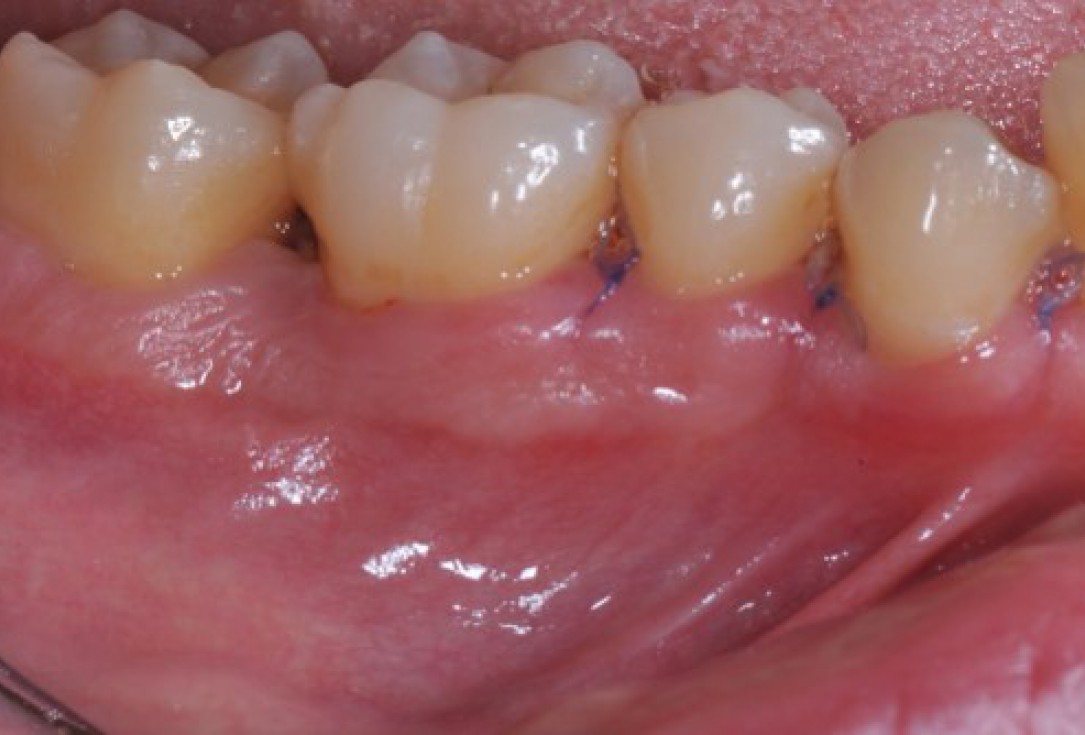

02/22 - Pre-surgical clinical situation, lingual view.

Deep intrabony defects treated using Straumann® Emdogain® - Dr. M. Stefanini